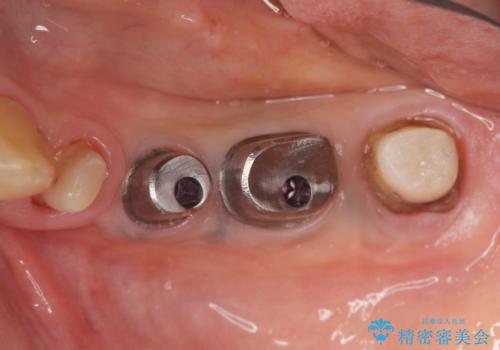

X線写真より、過度な咬合支持負担により支台となる歯の周囲の骨吸収が認められます。今後安定してしっかりとかめるような環境を整備するためにインプラント治療を選択しました。

- 100万円(ストローマンインプラント×2・仮歯×4・チタンカスタムアバットメント×2・ジルコニアクラウン×4)費用は治療当時の料金となります

ブリッジ治療は支台となる歯が弱いと、今回のように周囲の骨が吸収したり歯が割れてしまったりといったトラブルがおきます。咬合力に対抗するため、今回はインプラントを用いて機能回復を行いました。